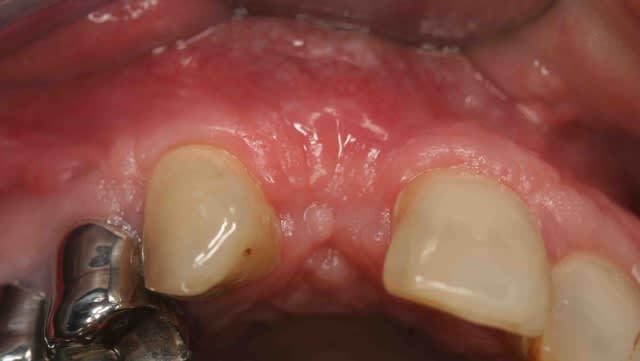

le protocole de Khoury basé sur ses parfaites connaissances du phénomène de cicatrisation permet d'obtenir des greffons de super qualité au moment de la mise en place des implants.

Screenshot015 copie ryteqf - Eugenol

Img 4922 dw6gpg - Eugenol

Img 4924 qsttsv - Eugenol